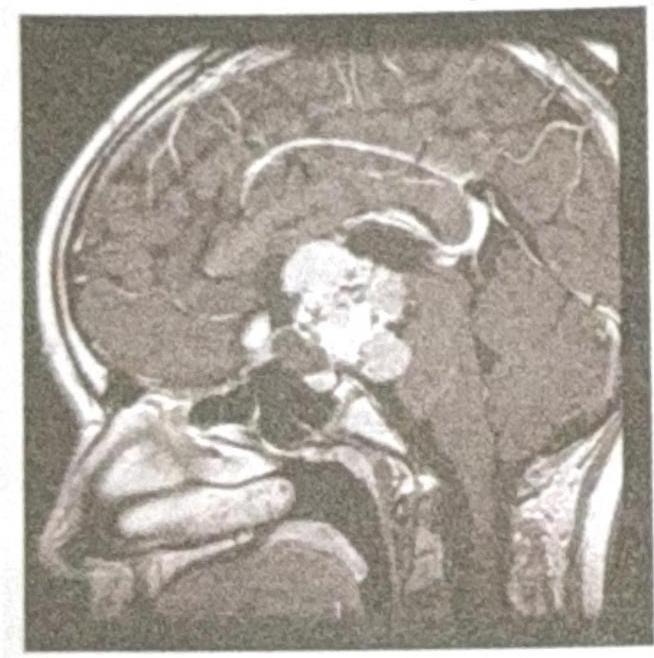

A 9-year-old female child presents with a history of headache and visual disturbances. What is the most likely diagnosis?

Explanation: ***Craniopharyngioma*** - Most common **suprasellar tumor** in children, presenting with the classic triad of **raised intracranial pressure** (headache), **visual field defects** (bitemporal hemianopia), and **endocrine dysfunction**. - Characteristic imaging shows a **suprasellar cystic and solid mass** with **calcifications** in 90% of childhood cases, distinguishing it from other sellar region tumors. *Pituitary macroadenoma* - Extremely rare in **pediatric population**, typically occurs in adults over 40 years of age. - Usually presents with **hormonal hypersecretion syndromes** (prolactinoma, growth hormone excess) rather than mass effect symptoms in children. *Hypothalamic hamartoma* - Primarily causes **gelastic seizures** (laughing spells) and **precocious puberty**, not typically headache and visual disturbances. - Appears as a **non-enhancing isodense mass** attached to the hypothalamus without calcifications or cystic components. *Optic glioma* - More commonly presents with **unilateral visual loss** and **proptosis** rather than bitemporal visual field defects. - Associated with **neurofibromatosis type 1** and appears as **fusiform enlargement** of the optic nerve without suprasellar calcifications.